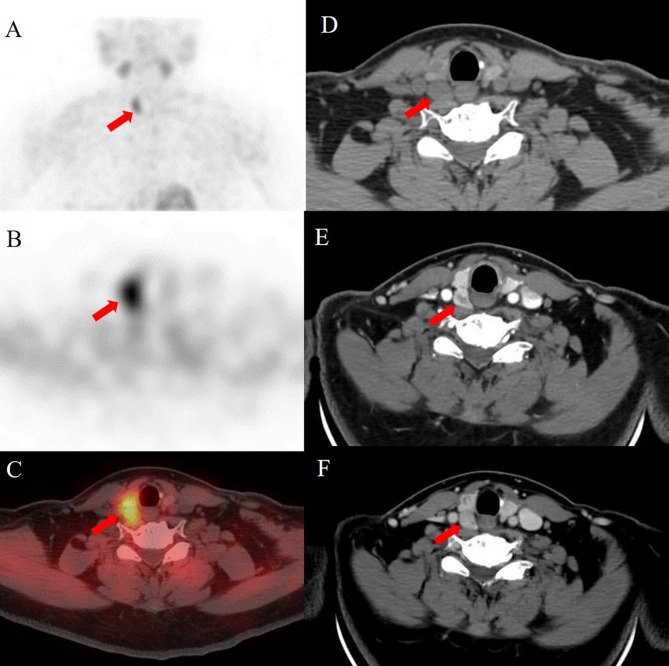

Objective: Accurate preoperative imaging localization is paramount to the success of targeted parathyroidectomy for primary hyperparathyroidism (PHPT). Four-dimensional (4D) CT is a promising method for preoperative localization of the parathyroid, but studies on the performance of 4D CT and technetium 99 m-sestamibi SPECT/CT for the diagnosis of diseases of the parathyroid are limited.

Materials and methods: To compare the diagnostic performance of sestamibi SPECT/CT and 4D-CT for preoperative localization in patients with PHPT in a single-institution from August 2017 to May 2024.

Results: Two hundred forty-two patients with PHPT (166 females; 52.5 years ± 13.4 [SD]) were evaluated. Among the 242 patients, 233 patients (96.3%) had single-gland disease, and 9 patients (3.7%) had multigland disease. Similar diagnostic performance was observed for sestamibi SPECT/CT and 4D-CT ([receiver operating characteristic ROC], 0.90 [95% CI: 0.87, 0.92] and 0.88 [95% CI: 0.85, 0.90], respectively; p = 0.11). Compared with 4D-CT, combined-modality sensitive reading and sestamibi SPECT/CT had the highest ROC, and, although there was no significant difference between the two (ROC, 0.91; 95% CI: 0.89, 0.93; p = 0.14), they significantly differed from 4D-CT (p = 0.0006). Sestamibi SPECT/CT showed an accuracy of 92% (95% CI: 90%, 94%), similar to 4D-CT (91%; 95% CI: 89%, 92%), combined-modality sensitive reading (91%; 95% CI: 89%, 93%) and combined-modality specificity reading (92%; 95% CI: 90%, 94%).

Conclusion: Sestamibi SPECT/CT has high accuracy in preoperative localization in patients with PHPT. Compared with sestamibi SPECT/CT alone, 4D-CT and combined-modality reading did not improve diagnostic performance.